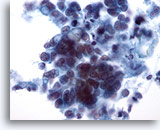

Figure 4: Breast FNA, Fibroadenoma. A large stromal fragment is present, containing a few small spindle-shaped nuclei. Stromal fragments may be seen in aspirates of benign breast tissue as well as in fibroepithelial lesions such as fibroadenoma. Stromal fragments from phyllodes tumors are much more cellular. Note the small group of benign ductal cells also present. 40x

Figure 4

Breast FNA, Fibroadenoma.

A large stromal fragment is present, containing a few small spindle-shaped nuclei. Stromal fragments may be seen in aspirates of benign breast tissue as well as in fibroepithelial lesions such as fibroadenoma. Stromal fragments from phyllodes tumors are much more cellular. Note the small group of benign ductal cells also present.

40x